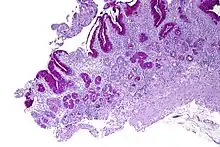

Micrograph showing nodular enterochromaffin-like cell hyperplasia, as demonstrated with chromogranin A immunostaining, in the body of the stomach. Parietal cells are not readily apparent. These changes are in keeping with autoimmune metaplastic atrophic gastritis, a histologic correlate of vitamin B12 deficiency anemia. | |

PA may be considered as an end stage of autoimmune atrophic gastritis, a disease characterised by stomach atrophy and the presence of antibodies to parietal cells and intrinsic factor.[36][37] Autoimmune atrophic gastritis, is localised to the body of the stomach, where parietal cells are located.[34] Antibodies to intrinsic factor and parietal cells cause the destruction of the oxyntic gastric mucosa, in which the parietal cells are located, leading to the subsequent loss of intrinsic factor synthesis. Without intrinsic factor, the ileum can no longer absorb the B12.[38] Atrophic gastritis is often a precursor to gastric cancer.[37]